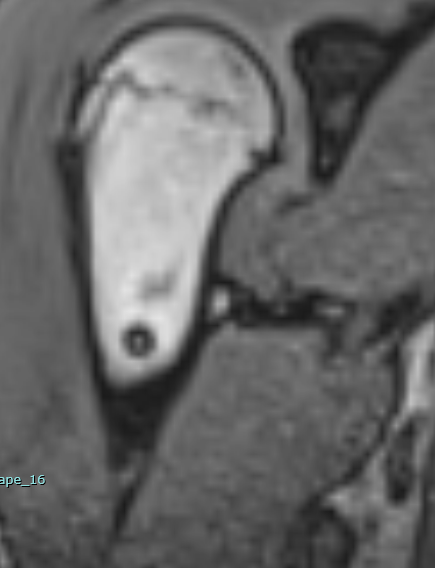

Tear of SSP and ISP?

Female 50 y.o. There is known tear of supraspinatus and infraspinatus tendon. Patient has frozen shoulder. Q1: It looks like incomplete full thickness tear of SSP, with rupture of the posterior aspect of tendon and extending to the infraspinatus? I am guessing there is tendinosis of the anterior aspect of SSP tendon but without rupture? Q2: Why the bone marrow of humerus is so bright on T2 SPAIR with prominent vessels? https://www.cmrad.com/cases/1786240110

1 like • Jul 29

I think this is a full-thickness tear mainly involving the anterior infraspinatus tendon but also some of the posterior suprapsinatus junctional fibers. I don't see how you could find any intact bursal or articular surface fibers. Definitely some underlying tendinosis. What further suggests this is more so infraspinatus is that there is already some degree of muscle bulk loss and infiltration into the infraspinatus, not much elsewhere. I agree the humeral head cysts are related to traction enthesopathy, particularly related to the infraspinatus, also noting there is some intrasubstance fluid/cyst formation dissecting into the infraspinatus muscle.

Given the location, I'd initially think this is an anchor from prior biceps tenodesis. But this doesn't really look like an anchor. If no prior surgical history, then it's probably an intraosseous cyst or some fibro-osseous lesion. Not aggressive or concerning in my opinion.